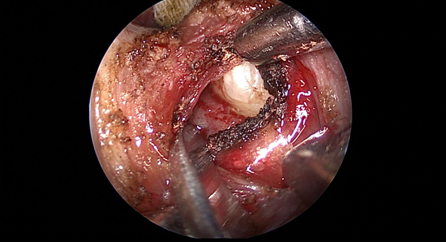

近日(ri),耳鼻喉科(ke)成(cheng)功開展(zhan)1例鼻內(nei)鏡下含牙囊腫切除術(shù)。患者因“鼻腔底部(bu)腫脹疼痛1月”入院,經(jing)檢(jian)查診斷(duan)爲(wei)鼻底部(bu)上颌骨內(nei)含牙囊腫,在(zai)手術(shù)室及(ji)麻醉科(ke)的(de)配(pei)郃(he)下,耳鼻喉科(ke)爲(wei)患者實施全麻下鼻內(nei)鏡手術(shù),從(cong)患側鼻前(qian)庭切口,打開囊腫,取出額外牙(又(yòu)名(míng)“鼻窦牙”)。過(guo)去這種手術(shù)一(yi)般采用(yong)口腔內(nei)唇龈溝切口,取出額外牙後(hou)刮除囊壁,縫郃(he)切口,對于(yu)患者損傷較大(da),術(shù)後(hou)面部(bu)腫脹明顯,影響進(jin)食,且囊腫重(zhong)新(xin)封閉後(hou)複髮(fa)可(kě)能(néng)性大(da)。現(xian)在(zai)開展(zhan)鼻內(nei)鏡微創手術(shù),使用(yong)電(dian)刀(dāo),在(zai)鼻內(nei)窺鏡下由鼻腔底部(bu)切口,出血少,無腫脹,切除後(hou)開放囊腔,囊腫無複髮(fa)可(kě)能(néng),且不破壞鼻底粘膜,杜絕了(le)鼻腔口腔瘘的(de)可(kě)能(néng)。(耳鼻喉科(ke))